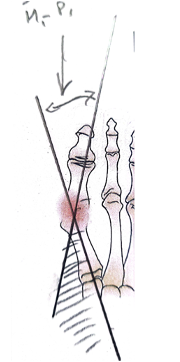

L’un des premiers éléments observés est l’augmentation de l’angle métatarso-phalangien, qui correspond à la déviation latérale du gros orteil. Progressivement, l’hallux s’oriente vers les autres orteils, ce qui perturbe son rôle normal dans la stabilisation et la propulsion du pied lors de la marche.

Parallèlement, on observe une augmentation de l’angle inter-métatarsien, qui traduit le déplacement du premier métatarsien vers l’intérieur du pied. L’écartement entre le premier et le deuxième métatarsien s’accentue, ce qui contribue à désorganiser l’alignement global du premier rayon.

La déformation est également favorisée par un déséquilibre des structures musculaires et tendineuses qui stabilisent l’articulation métatarso-phalangienne. Certains tendons, notamment ceux situés sur le versant latéral de l’articulation, peuvent exercer une traction qui accentue progressivement la déviation du gros orteil. Ce déséquilibre entretient et aggrave la déformation au fil du temps.

Rotation

Une rotation pronatrice du premier rayon est souvent associée à ces modifications. Dans ce cas, le premier métatarsien ne se contente pas de se déplacer vers l’intérieur, il effectue également une rotation sur lui-même. Cette composante rotationnelle est aujourd’hui reconnue comme un élément important de la déformation et peut être responsable de récidives si elle n’est pas correctement prise en compte lors du traitement chirurgical.

Enfin, la déformation entraîne souvent une subluxation des sésamoïdes, deux petits os situés sous la tête du premier métatarsien. Leur déplacement modifie l’équilibre de l’articulation et perturbe le fonctionnement normal du système d’appui.

Ces modifications peuvent également provoquer une altération de la répartition des charges sous l’avant-pied. Le premier rayon devenant moins fonctionnel, une partie des contraintes mécaniques se reporte vers les métatarses latéraux. Ce phénomène, appelé transfert de charge, peut entraîner l’apparition de douleurs sous l’avant-pied, parfois décrites comme des métatarsalgies.